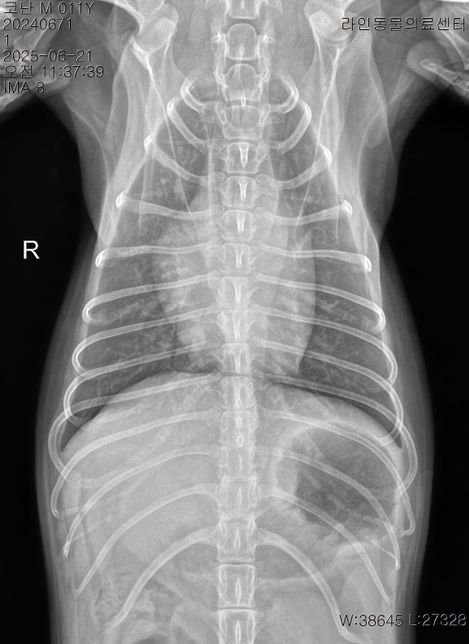

- 반려동물 건강반려동물Q. 강아지 이상증상 이유라도 좀 알고싶습니다..저희 강아지가 어제 아침부터 혀를 내밀고 과호흡에 혀가 보라색이 되고 배가 단단해지길래 바로 응급 병원에 갔더니 별다른 처치는 없었고 산소방에 30분에 있더니 배가 다시 물렁해지며 혀는 여전히 보라색이였으나 엑스레이와 호흡수가 정상이라하여 안정제/진정제 주사를 한대 맞았고 이제 안심을 하고 집에 왓는데 어제 저녁 9시경 애가 물설사와 사진처럼 점액변도 누고 밤 12시경 다시 점액변을 2차례 더 누고 새벽3시경 애가 낑낑거리며 봣더니 배가 다시 단단해져있었고 혀는 괜찮았고 호흡수만 괜찮았지만 하루 종일 잠을 못잤는데 다니던 24시 병원은 전화하니 잘 모르겠다고 솔직한 답변을 주셨고 새벽내내 이리저리 돌아만다녀서 아침에 다른 병원에 가서 엑스레이와 혈액검사 종양검사 등을 하니 저런 결과가 나왔고 이전 병원 엑스레이 사진을 보여드리니 폐침윤이 있어서 다시 엑스레이를 찍어보고 혈액검사도 해보니 심장과 폐문제는 아닌거같다 허리디스크 때문인듯하다 라고 하셨고 복부초음파는 해당 병원 장비가 갑자기 고장이 나서 되지가 않은 그런 상황입니다암은 아니라하고 특이한점은 crp 농도는 정상인데crp 는 13으로 높게 나왔습니다 오늘 찍은 엑스레이상 허리디스크가 심장과 폐 중앙 사이에 있는 허리디스크가 안좋았으며 췌장염은 리파아제 아밀라제가 괜찮다고 아닌거같다고는 하셨는데 cpLi 는 그래서 진행을 안한 상태입니다저도 강아지도 너무 지치는데요 오늘 하루종일 밥을 안먹은 상태이고 주사만 3대 진통제와 스테로이드(쿠싱상관별로없는 약한 스테로이드)를 맞은 상태입니다 대체 어떻게 해야할까요? 정말 허리디스크 때문일까요? 췌장염 가능성은 없을지 여쭤봅니다복부가 단단해지는 증상은 약 3개월전부터있었고 복명음 같은경우도 3개월전부터 있었는데 요즘은 그냥 하루종일 복명음이 들리고 소리도 점점 커지는 느낌입니다.허리디스크라 산책을 하면 안되지만 하도 애가 변을 안누길래 제가 가볍게 산책을 해주면 배가 다시 물렁해지는 그런 상황들이 여러번 있었고 2-3일전부터는 애가 식이알러지 증상도 나타났습니다 고추를 심하게 빨거나 ( 노란 고름이 나와서 항생제도 안에 넣는 세척을 오늘 진행하였고) 평상시에 포비돈으로 희석해서 멸균식염수와 같이 세척해줌에도 작년 9월부터 낫지를 않고 귀와 턱을 미친듯이 긁는 증상들도 있습니다정말 못고쳐도 좋으니 이유만이라도 좀 알고싶은데 병원에 가면 갈수록 저와 강아지는 지쳐만 갑니다한 병원에 계속 다니고 싶어도 첫번째 병원은 엑스레이만 찍고 혈액검사와 복부초음파를 요청하여도 호흡수와 엑스레이가 괜찮다고 그 어떤 처방도 받은것이 없어서 부득이하게 여러 병원들을 다니고 있는 상황인데 병원들이 가깝지도 않아서 차로 최소 1시간 거리들인 상황이라 정말 상상 이상으로 지치는데부디 혈액검사와 증상들을 살펴봐주시고 짐작이 가는 질병이나 췌장이나 대장쪽 문제는 없는지 알고싶습니다정장제와 허리디스크 약을 처방받은 상황이며 일주일동안 약을 먹어보고 그래도 이상하면 췌장이라고 들었습니다 참고로 아밀라아제 리파아제가 정상수치여도 초음파상 췌장에 에코가 있었던 이력이 있으며 심장 같은 경우는 b1 이라고 하고 청진도 잘 안들이기에 여러 병원들이 b2 는 아니라하였고 오늘 찍은 엑스레이에선 폐침윤은 없었습니다 다만 쿠싱이 살짝 의심은 된다고는 하였습니다 멏개월전에는 쿠싱검사시 cor 이 (1-6 이 정상인데 ) 인지 9 정도 나왔는데 몇개월후 오늘은 7.5 로 되었습니다 • T4-6 vertebrae의Rt. caudal articular process의defect 확인됩니다. (→)• T13-L1 vertebrae의IVDS(intervertebral disc space)가주변에비해좁게확인됩니다.(→• T13-L1 vertebrae의IVDS가주변에비해좁게확인되어IVDD 가능성고려됩니다. 신경계검사등추가적인신체검사추천되며, 신체검사상특이소견또는임상증상확인될경우척수실질평가를위한MRI 검사가추천될수있습니다.• T4-6 vertebrae의Rt. caudal articular process의dysplasia 확인되며, congenitalanomaly로고려됩니다. 이는, incidental finding으로고려되나, 척추의불안정성을야기하여IVDD를유발할수있습니다마지막 사진은 저희 강아지 작년 ct 촬영 사진입니다